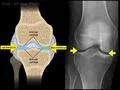

Dr. Morton explains the anatomy visible in knee X-rays, focusing on the AP, lateral, and sunrise views. He describes the bones and structures seen in each view, such as the femur, patella, tibia, fibula, and joint spaces. The AP view highlights the femoral condyles and tibial plateaus, while the lateral view shows the fabella and cruciate ligament attachments. The sunrise view focuses on the patella and trochlear groove. The video emphasizes the importance of smoothness and joint space in assessing knee health.